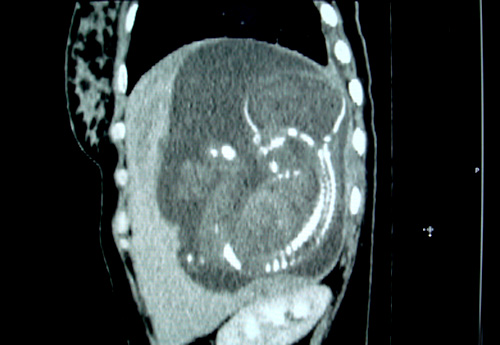

Một thai phụ nhập viện Từ Dũ trong tình trạng thai nhi nằm ở giữa thùy của lá gan bên trái thay vì nằm trong tử cung của người mẹ. Các bác sĩ đã phải tiến hành phẫu thuật nội soi để bóc tách khối thai nằm ở vị trí bất thường như thế.

Tại Bệnh viện Từ Dũ, qua kiểm tra các chỉ số trong máu, người bệnh được khẳng định đang mang thai nhưng nội soi ổ bụng không thấy khối thai. Mãi đến khi thai phụ được tiến hành nhiều biện pháp xét nghiệm, chẩn đoán hình ảnh khác mới phát hiện khối bất thường đường kính 60 mm ở mặt dưới phân thùy giữa gan trái, ép vào thùy đuôi của gan.

Khẳng định đây là trường hợp thai nằm sai vị trí hiếm gặp, có nguy cơ gây tổn thương động mạch chủ bụng, các bác sĩ đã tiến hành phẫu thuật nội soi để bóc tách khối thai nằm sai vị trí bất thường.

"Trường hợp này nếu không được phẫu thuật kịp thời, những gai nhau có thể xuyên thấu gan hoặc các mạch máu, đâm vào cuống gan làm tổn thương mạch máu, ống tụy bên trong khiến bệnh nhân tử vong", bác sĩ chuyên khoa II Nguyễn Bá Mỹ Nhi, Phó Giám đốc Bệnh viện Từ Dũ, cho biết.

Là bệnh viện sản tuyến cuối, đây là lần thứ hai các bác sĩ Bệnh viện Từ Dũ phát hiện trường hợp thai trong gan. Ca đầu tiên là một thai phụ 27 tuổi cũng ở Kiên Giang có bào thai nằm trọn trong gan. Theo các bác sĩ, trong các ca thai ngoài tử cung thì có đến 97% thai nằm ở vị trí vòi trứng. Chỉ khoảng 3% còn lại là các vị trí khác, trong đó, thai nằm ở khu vực gan là cực kỳ hiếm gặp.